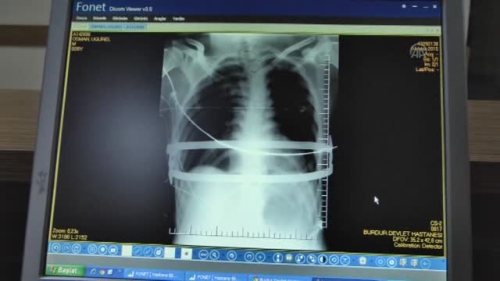

Göğsündeki çelik barlarla 2 yıl yaşayacak- Burdur'da göğsündeki çökme nedeniyle kalp ritm problemleri, çarpıntı ve nefes darlığı şikayetleri bulunan hasta, göğsüne takılan 100'er gramlık 2 çelik bar sayesinde sağlığına kavuştu- Hastanın göğsündeki barlar, iki yıl sonra çıkartılacak Burdur'da göğsündeki çökme nedeniyle rahatsızlık yaşayan hasta, göğsüne takılan 2 çelik bar sayesinde iyileşti.Burdur'da yaşayan 26 yaşındaki Osman Uğurel, halk arasında "kunduracı göğsü" olarak bilinen "pectus excavatum" hastalığı nedeniyle Burdur Devlet Hastanesine başvurdu. Doğuştan sternum (iman tahtası) çöküklüğü bulunan hastada kalp ritm problemleri, çarpıntı ve nefes darlığı problemleri belirlendi.Gerekli malzeme temini ve hazırlıklar yapıldıktan sonra hasta ameliyata alındı. Hastanın iki tarafından 3 santimetrelik kesiler açılarak 100'er gramlık 2 çelik bar, kalp ve iman tahtası arasından geçirilerek vücuda yerleştirildi ve çöküklük ortadan kaldırıldı. - "Çelik barlar iki yıl sonra çıkartılacak"Ameliyatı gerçekleştiren göğüs cerrahisi uzmanı Opr. Dr. Oktay Aslaner, gazetecilere yaptığı açıklamada, göğüs bölümünde çöküklüğün fazla olması nedeniyle 2 çelik bar kullanmak zorunda kaldıklarını söyledi. Yaptıkları tetkiklerde göğsün ön bölümündeki kemiğin kalbin üzerine çok ciddi baskı yaptığını gördüklerini anlatan Aslaner, şöyle konuştu: "Hastamızı en son yöntemle kapalı şekilde ameliyat ettik. Kalple iman tahtasının arasından bar geçirip daha sonra ters çevirerek öndeki kemiği yukarıya kaldırmış olduk. Hastayı ameliyattan bir gün sonra servise aldık. Şimdi taburcu olabilecek seviyede. Göğsündeki metaller 2 yıl kadar kalacak. Normalde bu hastaları biraz daha erken yaşlarda ameliyat etmek gerekiyor. Şimdi hem estetik olarak düzeldi, hem de bizim açımızdan önemli olan, kalbe ve akciğerlere yapılan bası ortadan kalkmış oldu."Aslaner, hastanın metallerden dolayı herhangi bir şey hissetmeyeceğini ve normal yaşamını devam edebileceğini kaydetti. - "Rahatsızlık hissetmiyorum"Hastanenin Kalp ve Damar Cerrahisi uzmanı Opr. Dr. Ulaş Sağlam ise hastayı hem göğüs hem de kalp ve damar cerrahisi olarak değerlendirdiklerini anlattı. Yaklaşık 1,5 saat süren ameliyatın başarılı geçtiğini ifade eden Sağlam, "Barların çeşitli boyutları vardı. Önce hastanın göğsüne koyacağımız barların ölçüsünü aldık. Ameliyata başlamadan bu ölçüye göre barlara şekil verdik. Daha sonra operasyonu gerçekleştirdik" dedi. Göğsüne çelik barlar konulan Uğurel ise ameliyattan sonra kendisini çok iyi hissettiğini dile getirdi.Uzun süredir kalp ritm problemleri, çarpıntı ve nefes darlığı şikayetleri olduğunu anlatan Uğurel, "Göğsümde doğuştan bir çöküklük vardı. Büyük sıkıntı yaşıyordum. Ameliyat iyi geçti. Metallerden dolayı ise vücudumda herhangi bir rahatsızlık hissetmiyorum" diye konuştu. .